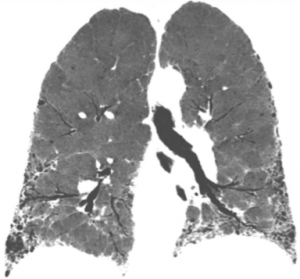

Las bronquiectasias son dilataciones anómalas e irreversibles de los bronquios cartilaginosos de tamaño mediano, que se acompañan de destrucción de los componentes muscular y elástico

La fibrosis pulmonar idiopática es la enfermedad pulmonar intersticial mas frecuente y no se conoce la causa que la provoca. Origina un endurecimiento o cicatrización